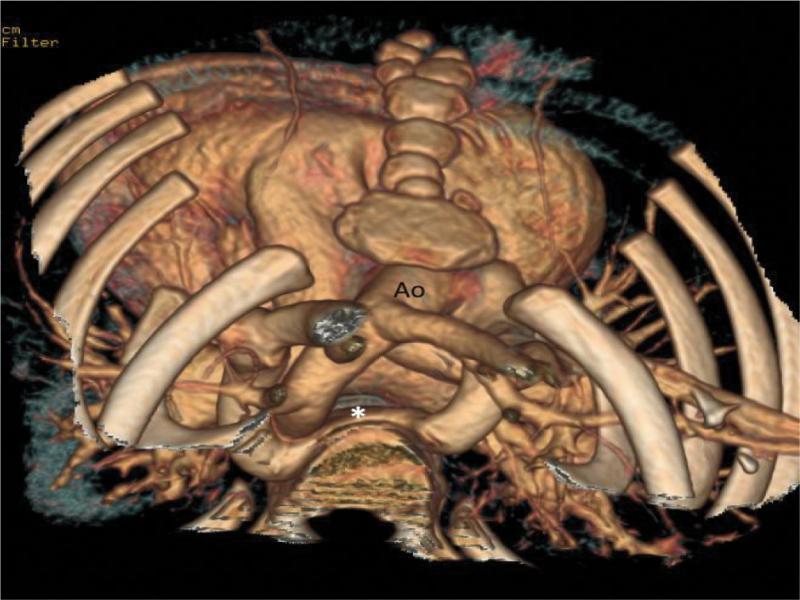

3D angiotomography reconstruction – posterior view, with removed bone elements of the posterior chest wall: vertebral column and ribs. In the foreground, a wide flattened venous vessel (V) located posteriorly from the descending aorta (Ao) is visualized. The vein is a continuation of the atypically running left brachiocephalic vein. Very clear deformation by adjacent thoracic vertebral bodies is seen; at this level, a relatively wide venous channel, probably the azygos vein, drains into the vessel from the bottom. Anomalous left innominate vein (V) joins the right brachiocephalic vein (RVBC) slightly above the junction with the right pulmonary artery (RPA). Normal drainage of pulmonary veins into the left atrium is clearly visualized. IVC – inferior vena cava